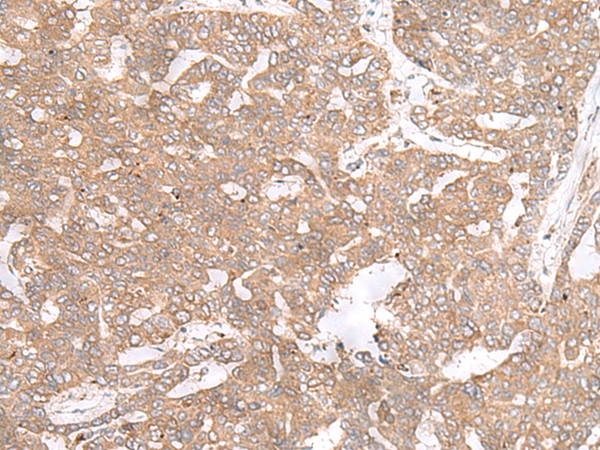

分类: 科研抗体货号: P09807别名: PIERCE1; RbEST47应用: IHC反应种属: Human